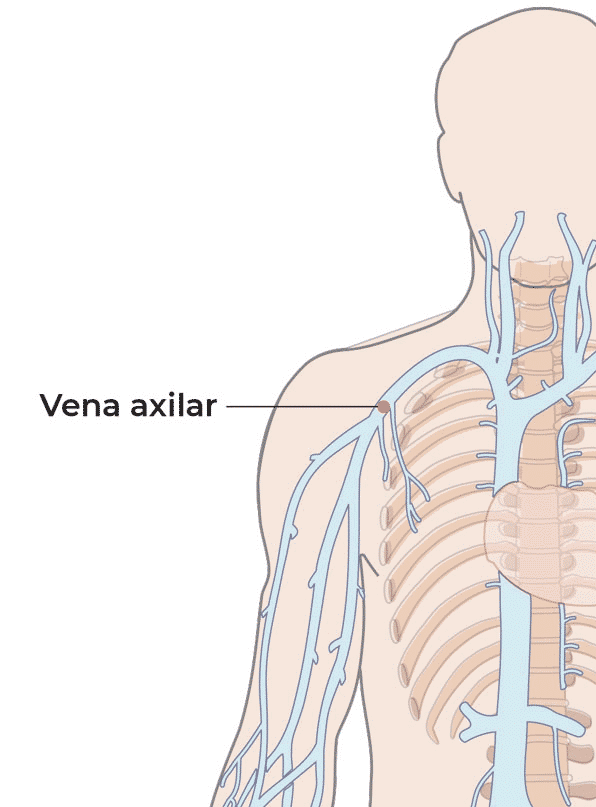

La línea media se inserta por encima de la fosa antecubital (en vena basílica o cefálica) y llega hasta la vena axilar: la punta se queda a una distancia media entre una localización periférica y una localización central.

Frente a las limitaciones del catéter corto periférico, la línea media permite un acceso vascular periférico que facilita el acceso a un calibre de vena suficiente grande como para evitar las complicaciones relacionadas con una localización muy periférica de la punta del catéter (flebitis, extravasación).